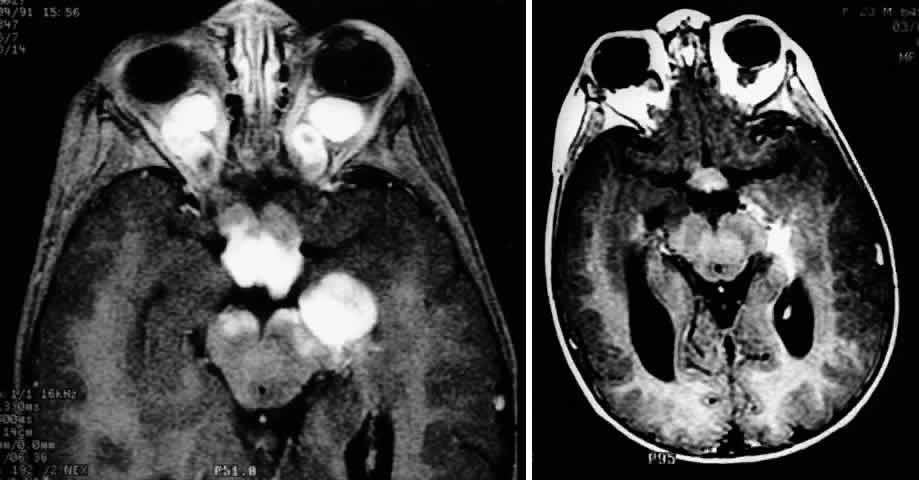

| Plain-film orbital X-ray may reveal concentric enlargement of the optic

Globular tumors in the suprasellar area that lack these features usually require craniotomy and biopsy confirmation. Lesions that may be difficult to distinguish from optic pathway gliomas include germinomas of the visual system and optic nerve choristoma because they both may appear intrinsic to the visual pathway.13 Tumors such as craniopharyngiomas and pituitary adenomas usually do not appear intrinsic to the visual pathway and may have features of sellar enlargement. Findings such as enhancement of the leptomeninges or peripheral enhancement of an enlarged chiasm are atypical of optic glioma and may indicate an inflammatory process masquerading as a glioma.83 Aneurysms in the suprasellar area may sometimes appear on neuroimaging to be intrinsic to the visual pathway. Better definition may be noted with magnetic resonance angiography.13 In contrast to orbital optic nerve gliomas, meningiomas enhance strongly with gadolinium and are less common in children. Meningiomas have the following features on axial CT scanning that are not typically shared by optic nerve gliomas: